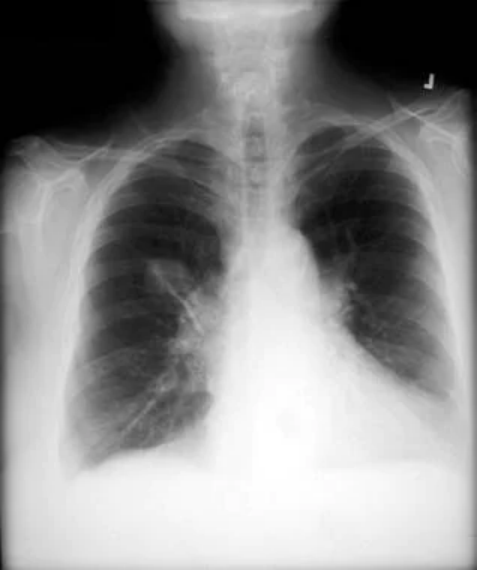

非小细胞肺癌。左上塌陷几乎总是继发于支气管内支气管癌。